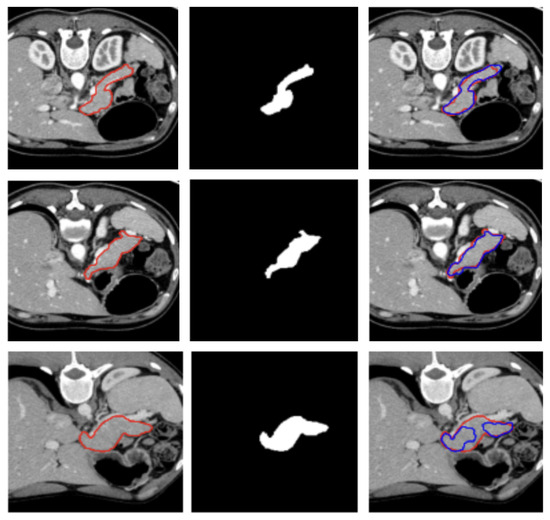

A visual representation of the segmentation obtained on a representative subject of the NIH dataset is illustrated in Figure 2.

Figure 2.

Visualization of two representative test samples from the NIH dataset showing: the input image with the pancreas ground truth overlaid as a red contour (left), the corresponding pancreas mask (center), and the output of the model overlaid to the input image as a blue contour (right). The first sample (first and second row) illustrates an easy case with clear organ boundaries and the second sample (bottom row) depicts a more challenging case with low contrast, yet the model still captures the main structure.

This result suggests that the model generalizes well to unseen data and is not overly sensitive to the specific distribution of training cases. The low standard deviation further confirms the stability of the training process and the effectiveness of the preprocessing, architecture design, and data augmentation strategies employed.

Figure 2 and Figure 3 show, qualitatively, the results of our attention-based 3D U-Net model trained on NIH and MSD datasets, respectively, with a combined Focal and Dice loss. The figures show across different sample cases, how the model successfully delineates the pancreas with high spatial accuracy, as demonstrated by the strong alignment between predicted and ground truth contours. The use of Dice loss contributed to the precise overlap in the segmented regions, while Focal loss improved the model sensitivity to challenging areas, especially along class boundaries where the pancreas is thin or adjacent to low-contrast structures. Notably, even in slices where the pancreas is partially obscured or appears small and fragmented, the model maintains accurate contour predictions. This suggests that the attention mechanism effectively focuses on relevant anatomical regions, suppressing background noise and enhancing feature discrimination.

These visual results support the quantitative performance of the model reported in Table 1 and Table 2 and demonstrate its ability to produce reliable and anatomically consistent pancreas segmentation in volumetric CT data.